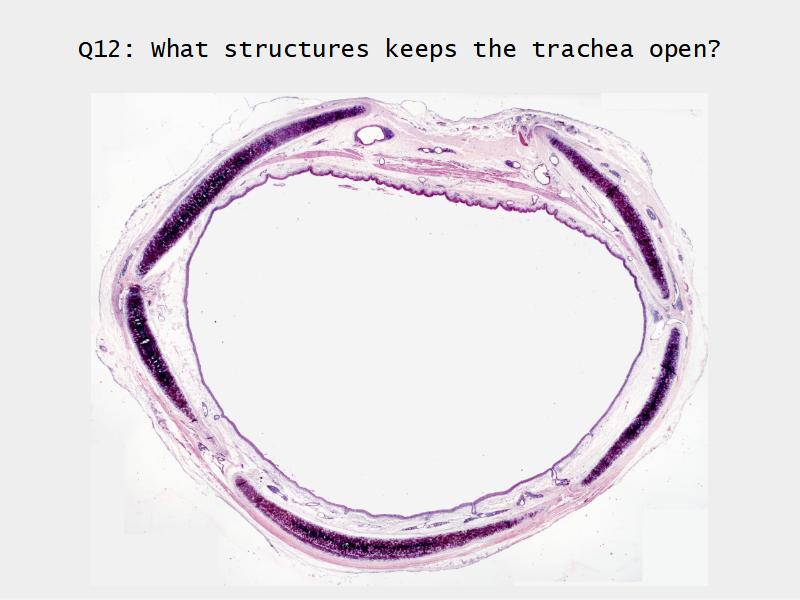

Trachea

Bronchi - Transitions

- Intrapulmonary bronchi

- Irregular cartilage

- Respiratory epithelium

- Glands

- Bronchioles

- Smooth muscle REPLACE cartilage